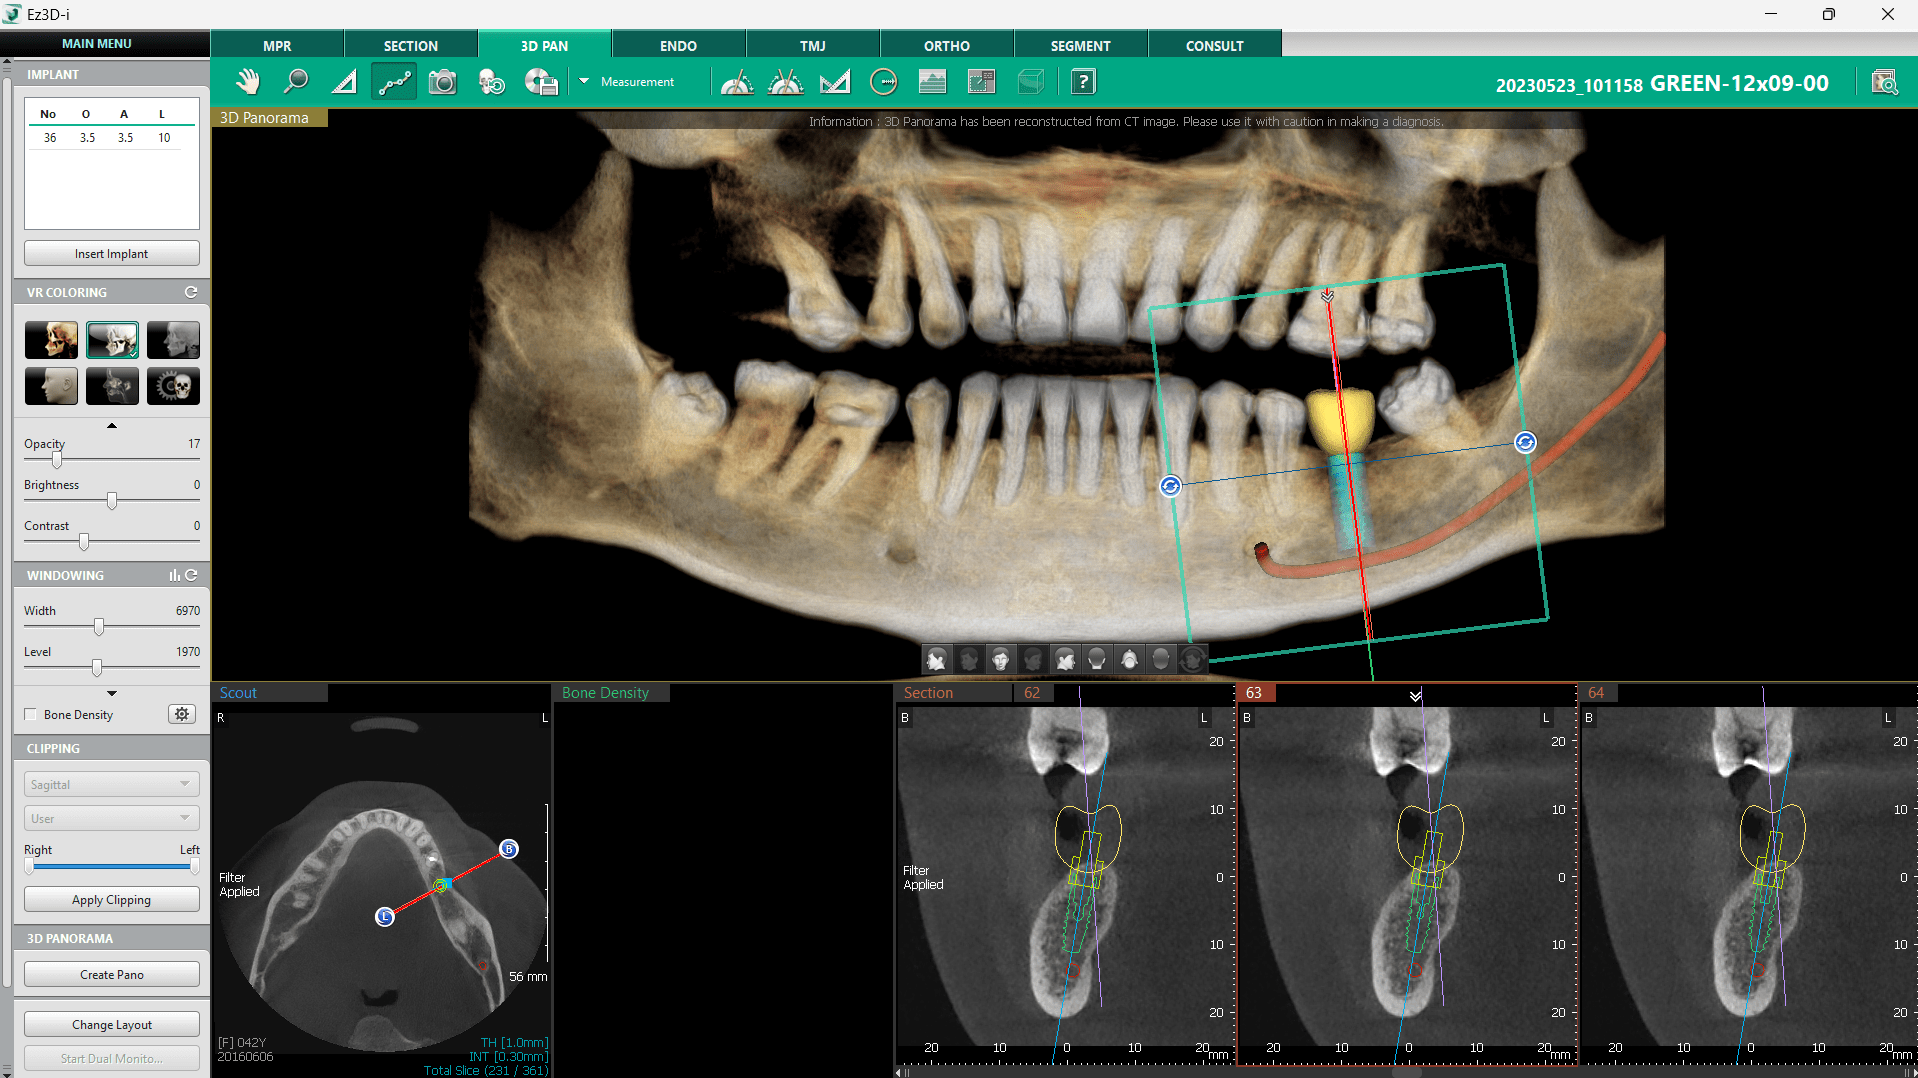

Localizarea canalului mandibular este esențială pentru stabilirea unei abordări corecte în planificarea implanturilor. Software-ul Ez3D-i oferă mai multe metode pentru marcarea acestuia în imaginile 3D, iar utilizarea 3D PAN reprezintă una dintre cele mai rapide și eficiente modalități. Combinarea 3D Navigator cu imaginea panoramică 3D, generată dintr-o scanare CT, oferă o modalitate rapidă de a naviga prin secțiuni și de a localiza canalul.

Procesul începe prin selectarea opțiunii „Draw Canal” din bara de instrumente din partea de sus a ecranului și inițierea trasării de la foramen mentale, punctul optim pentru începutul delimitării canalului mandibular. 3D Navigator joacă un rol important în acest proces, facilitând identificarea precisă a canalului. Odată găsit, canalul poate fi marcat cu ajutorul butonului stâng al mouse-ului, iar navigarea prin secțiuni se poate face utilizând rotița de scroll. În cazul unei erori, punctele trase anterior pot fi șterse rapid cu printr-un click pe butonul drept al mouse-ului.

După completarea trasării, linia canalului se finalizează printr-un dublu click, iar dacă este necesară o ajustare, traseul poate fi editat sau șters în orice moment printr-un click dreapta pe linie. Această funcție oferă medicilor siguranța că implanturile pot fi plasate în poziția optimă, minimizând riscurile de afectare a structurilor nervoase.

Funcția „Profile” este un instrument simplu și eficient care permite evaluarea densității osoase într-o secțiune specifică. Aceasta utilizează tabul 3D Pan și 3D Navigator pentru a localiza poziția viitorului implant și pentru a afișa secțiuni relevante ale osului.

După identificarea zonei de interes, se poate selecta opțiunea „Profile” din bara de instrumente din partea de sus a ecranului sub meniul Measurement și trasarea unei linii în secțiunea imaginii la locul viitorului implant. Se va genera automat un grafic al densității osoase în acea zonă. Acest grafic oferă o evaluare preliminară, iar în cazul unor rezultate nesatisfăcătoare, se pot efectua examinări suplimentare pentru a determina necesitatea unor proceduri de augmentare osoasă.

În cazul prezentat în acest articol, pacientul părea a fi într-o stare buna, iar medicul a continuat cu pregătirile.